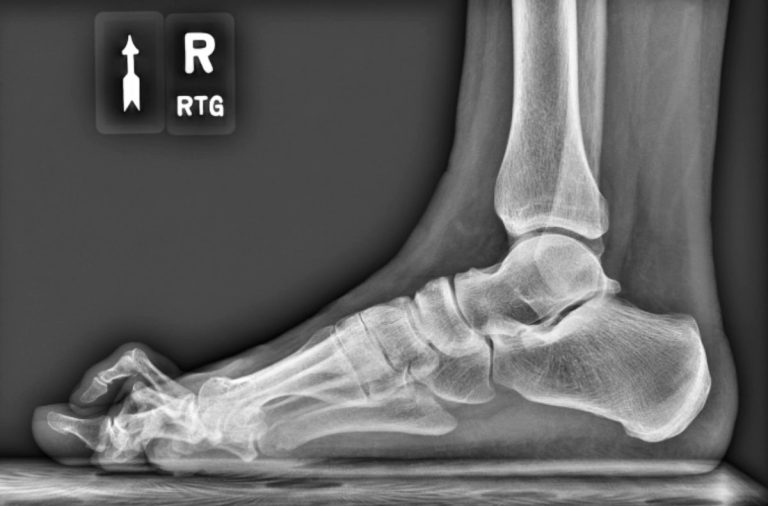

Badanie obrazowe i wizualizacja struktur anatomicznych układu mięśniowo-szkieletowego.

Chirurgia stawu skokowego i stopy

W Form zajmujemy się także ortopedią – nie tylko samą diagnozą i leczeniem schorzeń, ale także profilaktyką. Pomożemy Ci w przypadku schorzeń ręki i nadgarstka, łokcia, barku, biodra, kolana czy stawu skokowego i stopy. Posiadamy kadrę wykwalifikowanych lekarzy, specjalistów ortopedii i traumatologii, którzy specjalizują się w osobnych grupach chorób – masz więc pewność, że zgłaszając się do nas np. z chorobą barku, trafiasz pod opiekę odpowiedniego specjalisty. Oferujemy Ci wszelkie znane współczesnej ortopedii metody leczenia zachowawczego, operacyjno-zabiegowego i diagnostyki. W naszej klinice ortopedii wykonasz np. RTG, tomografię komputerową, rezonans magnetyczny (także z kontrastem), czy USG.